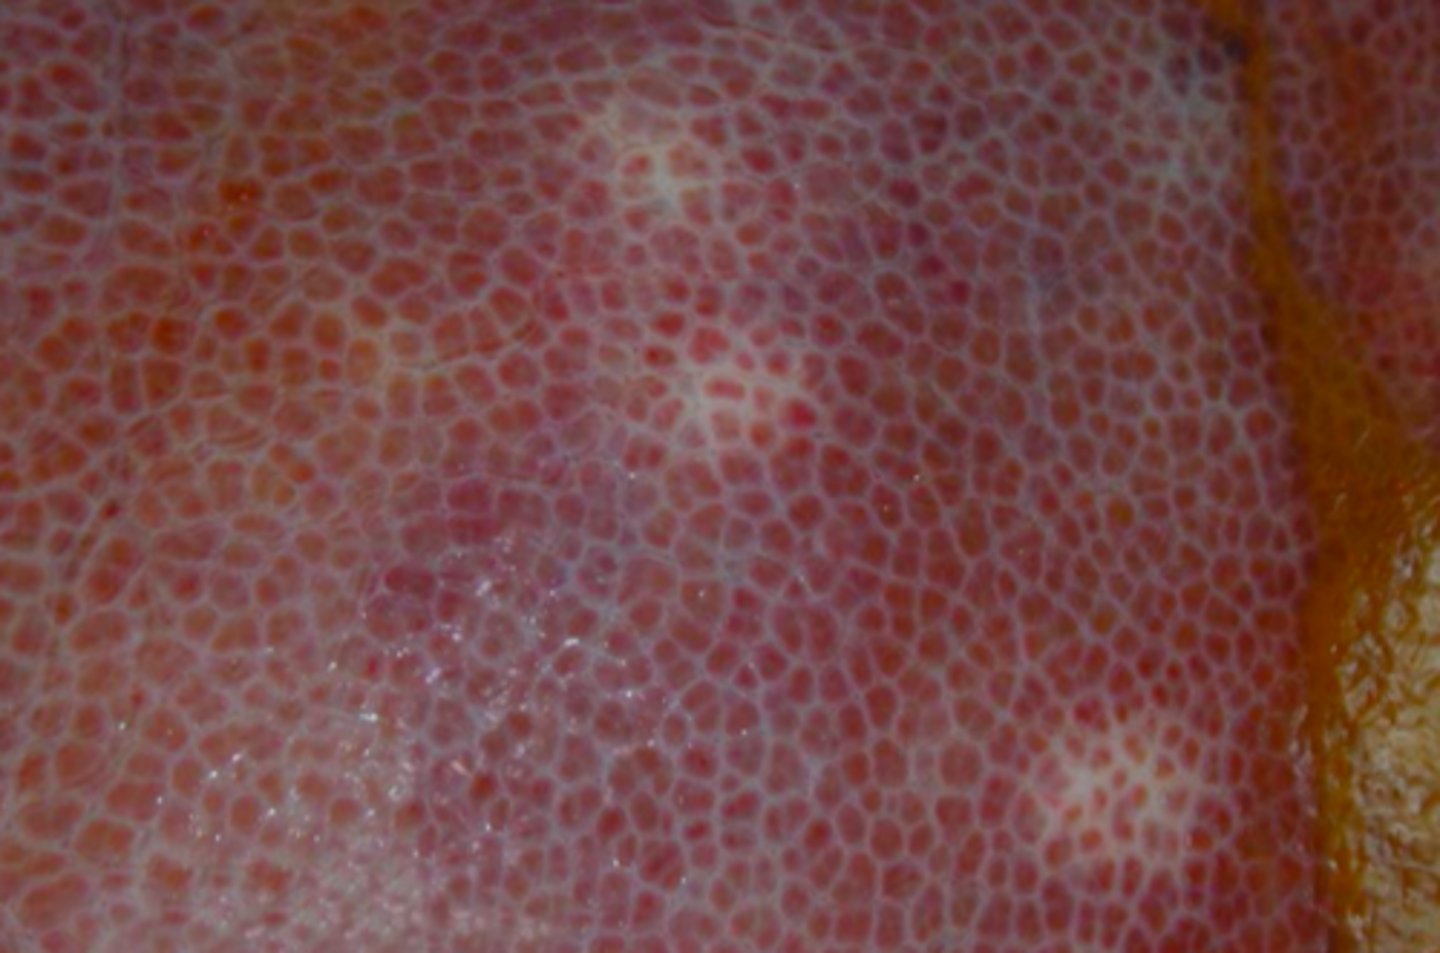

Diffus Steatosis (hepatis)

leveren bliver lys og gullig med buttede rande og har nedsat tekstur

Lever fra okse, hvad er den patoanatomiske diagnose?

diffus ophobning af synligt fedt i form af triglycerider i hepatocytterne

Hvad ophobes i leveren ved Steatosis hepatis?

forandringer i form af infektionssygdomme, overfodring, øget mobilisering fra depoter (sult), nedsat metabolisering af kulhydrater (ketose), nedsat fedtmetabolisering i hepatocytterne (ses ved nedsat ilttilførelse og toksiner), lipæmi hos især ponyer, koboltmangel hos får, endokrin forstyrrelser (fx diabetes mellitus eller hypothyreoidisme)

Hvad skyldes Steatosis hepatis? (mange årsager)